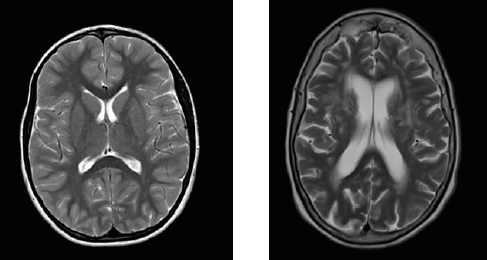

Imágenes de resonancia magnética: cerebro de una persona joven vs cerebro de una persona mayor con malos hábitos

Izquierda: corte axial (o sea como la tajada de un banano) del cerebro de un paciente de 35 años sin daño en su sustancia blanca. Derecha: corte axial del cerebro de un paciente de 70 años con muchas manchitas blancas en la sustancia blanca, como consecuencia del daño vascular prolongado, lo que se conoce como microangiopatía; también el volumen cerebral ha disminuido, o sea que ha perdido miles de neuronas.